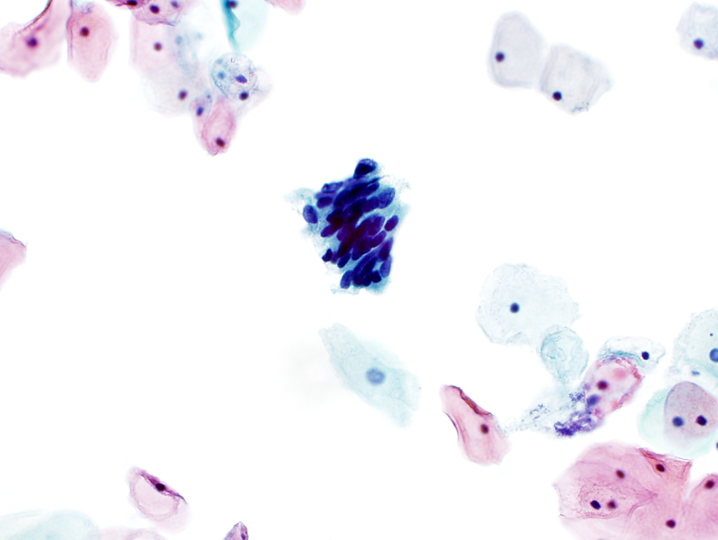

- Atypical endocervical cells, NOS

- Cells occur in sheets and strips with some cell crowding, nuclear overlap or pseudostratification

- Nuclear enlargement and increased N:C ratio

- Anisonucleosis

- Mild nuclear hyperchromasia and chromatin irregularities

- Occasional nucleoli

- Rare mitotic figures

- Distinct cell borders

- Atypical endocervical cells, NOS

Cytology images

A. Atypical glandular cells, favor neoplastic. The image shows endocervical cells with crowding, nuclear overlap, hyperchromasia and focal feathering. Answers B, C and D are incorrect because cytologic features of endometrial adenocarcinoma, HSIL and tubal metaplasia are not seen.